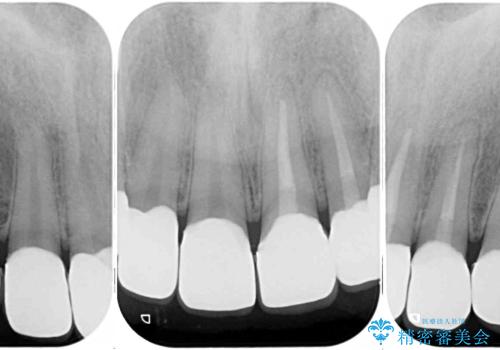

- むし歯の影響で、前歯を見せることが恥ずかしいとのことで来院された患者様です。

全顎的にむし歯が多く、治療が必要な歯はたくさんありましたが、まずは非常に目立つ前歯から処置を行うこととしました。

むし歯は歯肉内にまで進行していると外科処置が必要となりますが、ギリギリの位置でとどまっていたため、速やかにオールセラミッククラウンにて補綴治療することとしました。